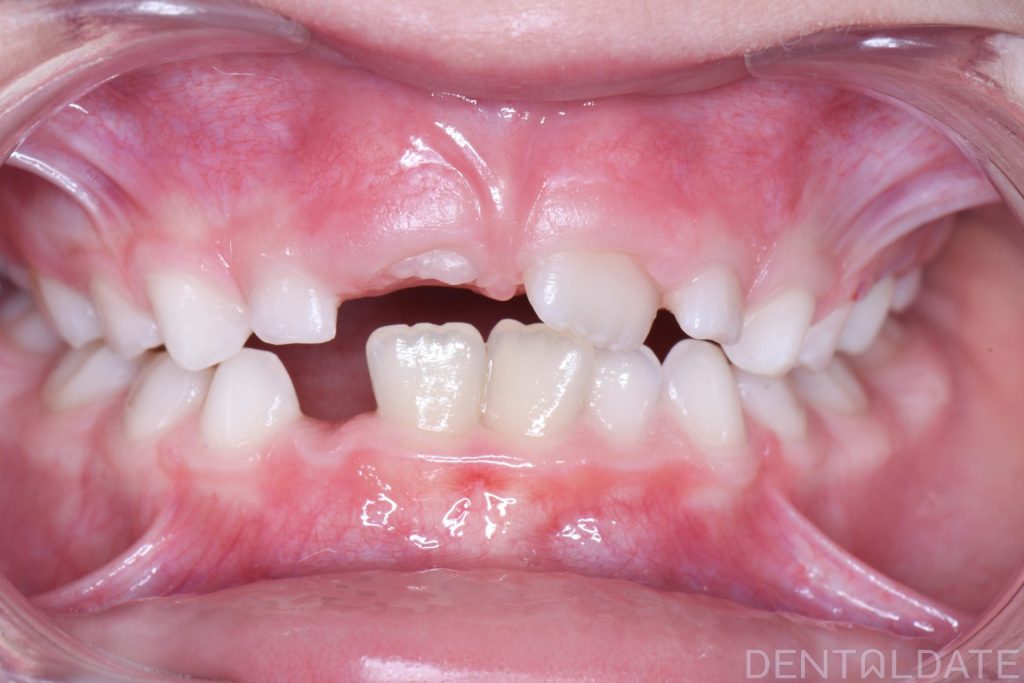

In this case, there was a severe lack of space for the permanent teeth, narrowing of the upper jaw, and the development of a malocclusion.

A Haas appliance was placed as the first stage of treatment, followed by the use of a myofunctional appliance.